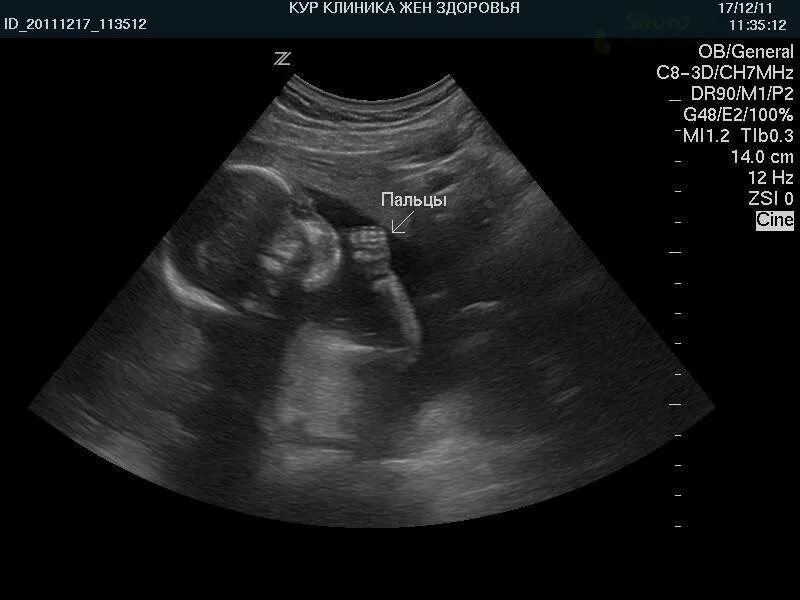

22 неделя тянет живот